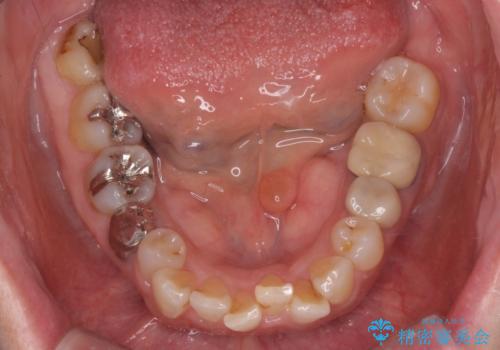

骨隆起除去

- 骨隆起が舌にあたり不快感があるので骨隆起をとりたくて来院。

静脈内鎮静麻酔下で骨隆起を除去を行いました。

骨隆起がなくなり不快感がなくなり大変満足して頂けました。